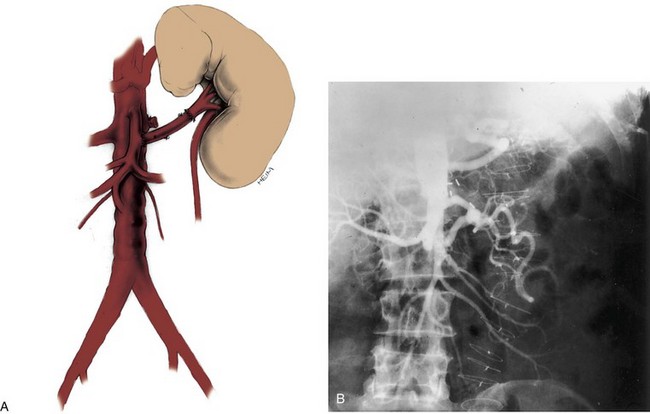

Frequent anatomic variation in the renal vasculature contributes to the complexity of open renal surgery. Multiple renal arteries, which typically arise from the aorta or iliac arteries, are the most common variation, occurring in 25% to 30% of the population (Merklin and Michels, 1958; Boijsen, 1959; April, 1997). Supernumerary hilar renal arteries originate at the aorta adjacent to the renal artery and traverse the renal hilum, whereas polar renal arteries originate at a greater distance from the main renal artery and enter the renal parenchyma directly. Ectopic and horseshoe kidneys more frequently have supernumerary renal arteries (Fig. 54–11).

Figure 54–11 Horseshoe kidney with multiple arterial branches well defined with three-dimensional imaging.